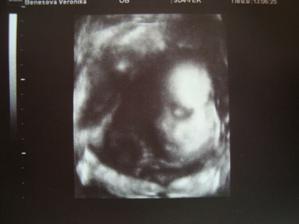

19.3.2011 - dnes jsme byli i s tatínkem na 3D a ta naše prďolka je tajnůstkářka.🙂)...tak už se začíná lišit od Nikolky..🙂..nemáme jedinou pěknou fotečku obličeje, celou dobu byla opět nalíplá na placentě, takže obličej nám zůstal utajen...☹...nožičkama je pořád dole..jo a má přesně půl kila..🙂)

11.4.2011 (27tt) - takže, za necelý měsíc nám Terezka přibrala půl kila!!!takže se z ní pomalu a jistě stává cvalíček...takže máme rovné 1 kilo...🙂))..dr nám dělal znovu 3déčko a tentokrát bylo i něco malinko vidět - a je ooopět celá tatínek..🙂) (maminka má +5kg)